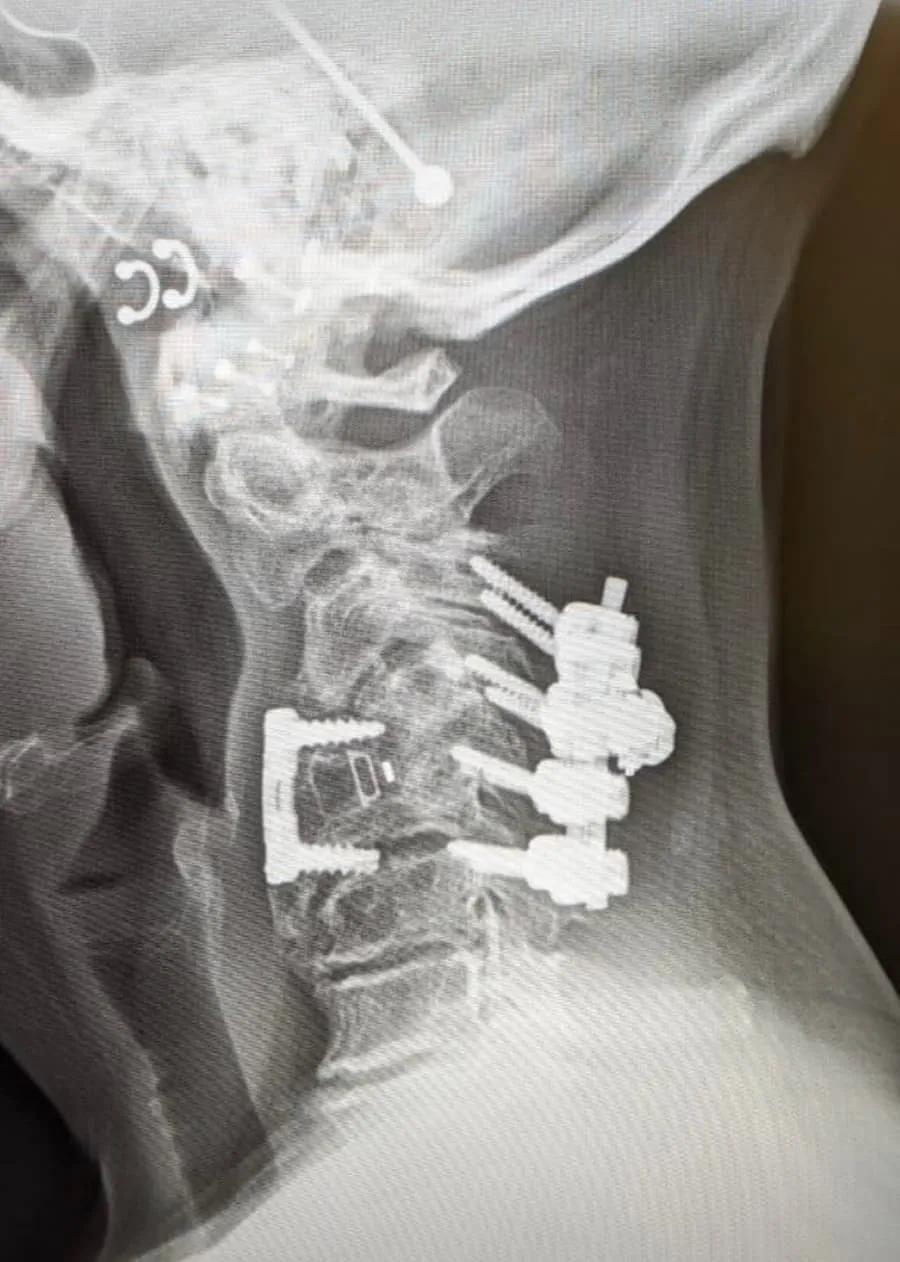

X-ray of a spine with surgical rods and screws implanted along the vertebrae.

90%+ Need Additional Surgery